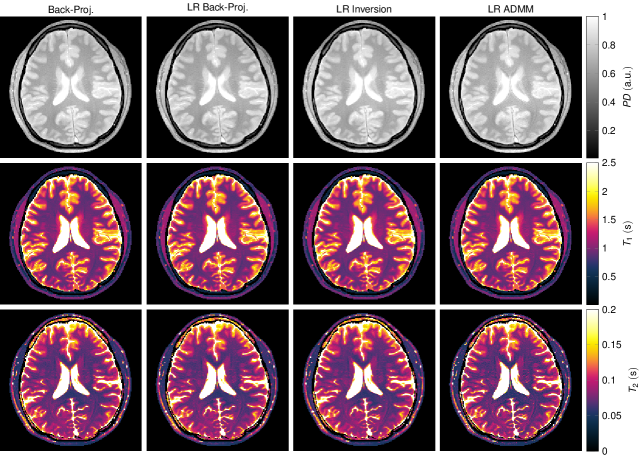

The in vivo maps reconstructed from one radial spoke per Tโ€‹R๐‘‡๐‘…TR (Fig. 10) appear noisy when reconstructed with the standard back-projection and the low rank back-projection. However, the artifact level is reduced compared to the simulations. Since the data were acquired with a multi-coil array, the back-projection includes a multiplication with the complex conjugate of the coil sensitivity profiles. Even though this does not represent a parallel imaging algorithm, it still mitigates the undersampling artifacts to some extent. An improvement of the reconstruction quality can be observed when employing a low rank inversion and particularly when using the proposed low rank ADMM reconstruction. However, the noise level is still high, especially in the T2subscript๐‘‡2T_{2} map. This can be attributed to the short acquisition time (4.1โ€‹s4.1s4.1\leavevmode\nobreak\ \text{s}) in combination with a suboptimal acquisition pattern. A similar effect can also be observed in the simulation data shown in Figs.ย 2f and 7, which also show a relatively high variability in the T2subscript๐‘‡2T_{2} maps. Measuring the mean and standard deviation over a region of interest in the frontal white matter shows a decrease in the standard deviation when employing the proposed LR ADMM algorithm (Tab.ย 1). Note that the mean values are affected by slice profile imperfections and magnetization transfer effects.

Figure 10

The depicted parameter maps with a matrix size of 192ร—192192192192\times 192 were reconstructed from 841 radial spokes, which were acquired in vivo within 4.14.14.1ย s. Coil sensitivity profiles of a 16 channel head coil (compressed to 8 virtual coil elements) were incorporated. The red rectangle at the top left indicates the region of interest in which mean and standard deviation of the relaxation times were calculated (Tab.ย 1). Note that the relaxation times are biased by slice profile imperfections and by magnetization transfer effects.

Figure 10: The depicted parameter maps with a matrix size of 192ร—192192192192\times 192 were reconstructed from 841 radial spokes, which were acquired in vivo within 4.14.14.1ย s. Coil sensitivity profiles of a 16 channel head coil (compressed to 8 virtual coil elements) were incorporated. The red rectangle at the top left indicates the region of interest in which mean and standard deviation of the relaxation times were calculated (Tab.ย 1). Note that the relaxation times are biased by slice profile imperfections and by magnetization transfer effects.